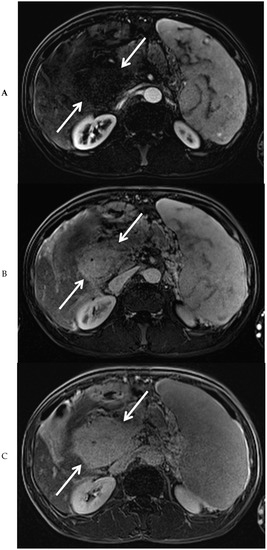

Figure 3.

Magnetic resonance imaging of the mass in the upper abdomen (arrows). Shown are T1 weighted subtraction images of the mass in the upper abdomen with fat suppression after administration of intravenous contrast medium in the arterial (A), portal venous (B), and delayed phase (C). At magnetic resonance cholangiopancreaticography, narrowing of the common bile duct is visible along its complete course (arrows), combined with dilation of the intrahepatic bile ducts (arrowheads) (D). At T2-weighted imaging (E, coronal view), the mass surrounding the narrowed common bile duct was slightly hyperintense, when compared to the liver parenchyma (arrows).